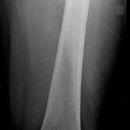

Oberschenkel a.p.

Patient in Rückenlage, Bein leicht abgespreizt, Fußspitze nach innen rotiert.

Senkrecht auf Oberschenkelmitte d.h. Femur

1. proximaler Oberschenkel: mit Darstellung der Hüfte, oberer Kassettenrand 2 QF oberhalb der Spina bzw. Lichtvisier bis Spina.

2. distaler Oberschenkel: mit Darstellung des Knies, unterer Kassettenrand 4 QF unterhalb der Patella.

Bei Erwachsenen soll das Hüftgelenk a.p. orthograd mit abgebildet sein. Bei distaler Aufnahme muss das Kniegelenk orthograd getroffen werden.